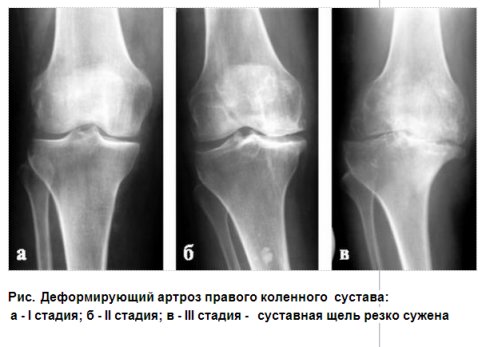

Среди отечественных ортопедов наибольшее распространение получила классификация деформирующего артроза, предложенная Н. С. Косинской (1961), согласно которой в течение патологического процесса различают три стадии.

I стадия (рис а) - неравномерное сужение суставной щели по сравнению со здоровым суставом и легкий остеосклероз;

II стадия (рис б) - появление краевых костных разрастаний (остеофитов), сужение суставной щели в 2-3 раза больше нормы, выраженный субхон-дральный склероз;

III стадия (рис в) - почти полное исчезновение суставной щели, расширение суставных поверхностей за счет обширных краевых костных разрастаний, деформация сустава, склерозирование суставных поверхностей, нередко их фрагментация и субхондральный очаговый некроз в виде кистозных просветлений или полостей.